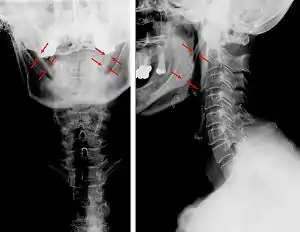

![]() | |

| Anteroposterior and lateral radiographs of cervical spine showing ossification of the stylohyoid ligament on both sides | |

Radiograph, lateral view showing elongated stylohyoid process and stylohyoid ligament ossification

Radiograph, lateral view showing joint-like formation in ossified stylohyoid ligament

Imaging is important and is diagnostic. Visualizing the styloid process on a CT scan with 3D reconstruction is the suggested imaging technique.[12] The enlarged styloid may be visible on an orthopantogram or a lateral soft tissue X ray of the neck.